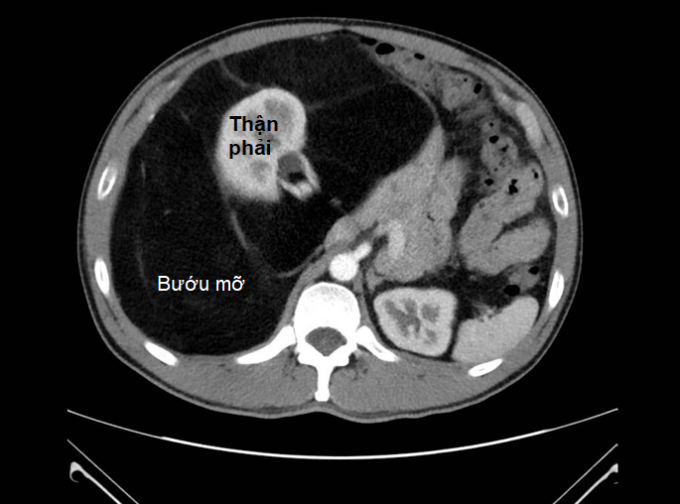

Ngày 14/5,BS.CK2 Nguyễn Phúc Minh,Trưởng Khoa Ngoại tiêu hóa,Bệnh viện Bình Dân,cho biết khối bướu đường kính 40 cm,cấu trúc tương đồng với mô mỡ,chiếm gần toàn bộ ổ bụng và bao quanh thận phải. Điều nghiêm trọng là bướu dính và chèn ép các mạch máu lớn như động mạch,tĩnh mạch chủ bụng và các mạch máu lân cận làm suy giảm chức năng thận.

CT bụng cho thấy bướu choán toàn ổ bụng,thận phải đã bị bướu mỡ bao xung quanh. Ảnh: Bệnh viện cung cấp